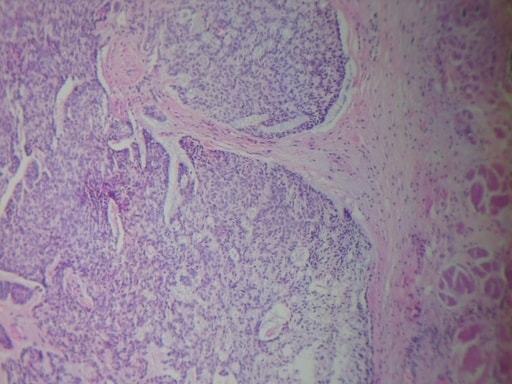

CARCINOMA MUCOCUTÁNEO